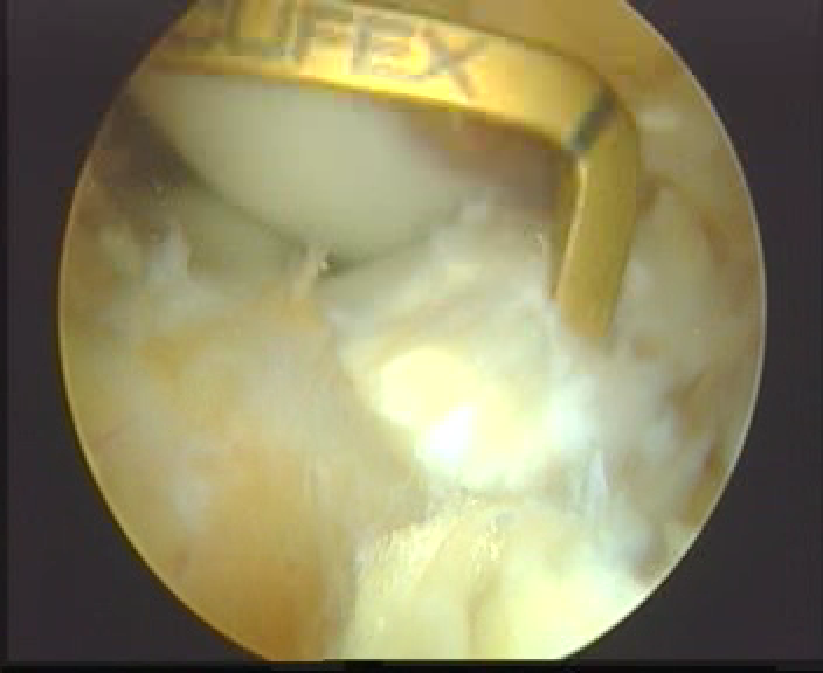

辅助内侧入路钻PL股骨隧道

屈曲90 °,导针在前侧关节软骨边缘后方5-7MM,上方3MM进入,屈曲110 °钻隧道。用直径6或7MM的钻头。

AM股骨隧道:在PL后侧边缘后方大约2MM,可以由胫骨隧道建立,直径一般7-8MM。

植入:先PL后AM

重建术后双束图